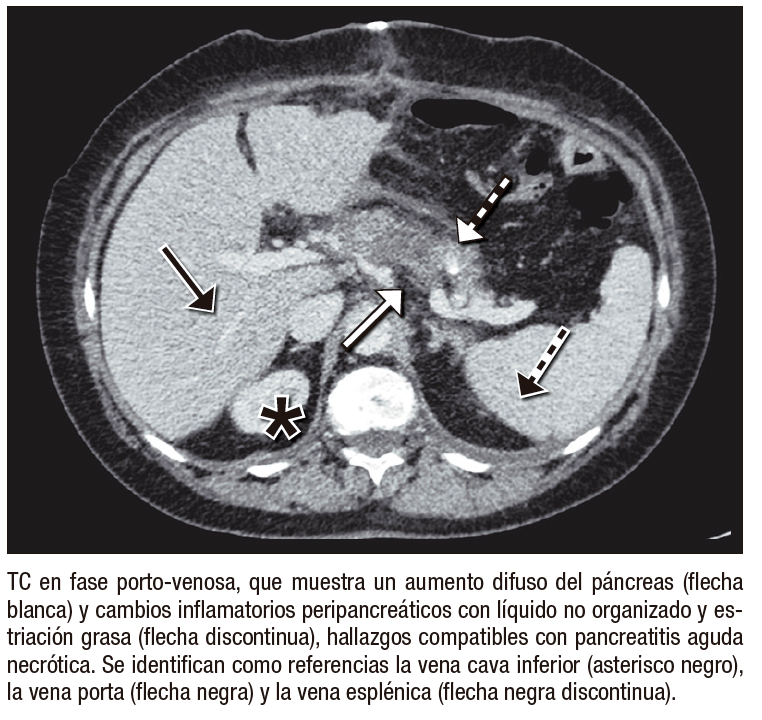

●Caso 4. Mujer de 72 años sometida a gastrectomía total con linfadenectomía por adenocarcinoma gástrico. En el período posoperatorio presentó dolor abdominal persistente, acompañado de elevación de enzimas pancreáticas. Ante la sospecha de pancreatitis aguda grave se efectuó una TC de abdomen y pelvis, que confirmó el diagnóstico. La paciente fue manejada en unidad de cuidados intensivos con terapia de soporte, evolucionando favorablemente.

Entre las complicaciones tempranas, la filtración anastomótica es una de las más graves, con incidencia reportada del 1% – 10% y elevada mortalidad.5 La TC es más sensible que el tránsito baritado para detectar colecciones con gas y extravasación de contraste.6, 7 La hemorragia posoperatoria, aunque infrecuente (0,5% – 5%), constituye una emergencia vital; la TC permite detectar hematomas y extravasación activa en fase arterial.8 La fístula entero-quilosa es poco común y secundaria a lesión linfática durante la linfadenectomía; en TC puede manifestarse como líquido hipodenso o colecciones con nivel líquido-graso.9 La pancreatitis aguda posoperatoria, generalmente relacionada con manipulación quirúrgica o compromiso vascular, puede confirmarse con TC mediante la identificación de necrosis focal y cambios inflamatorios.10 Finalmente, el infarto omental se observa como una masa grasa heterogénea con estriación del tejido adiposo, simulando absceso o recurrencia tumoral.11